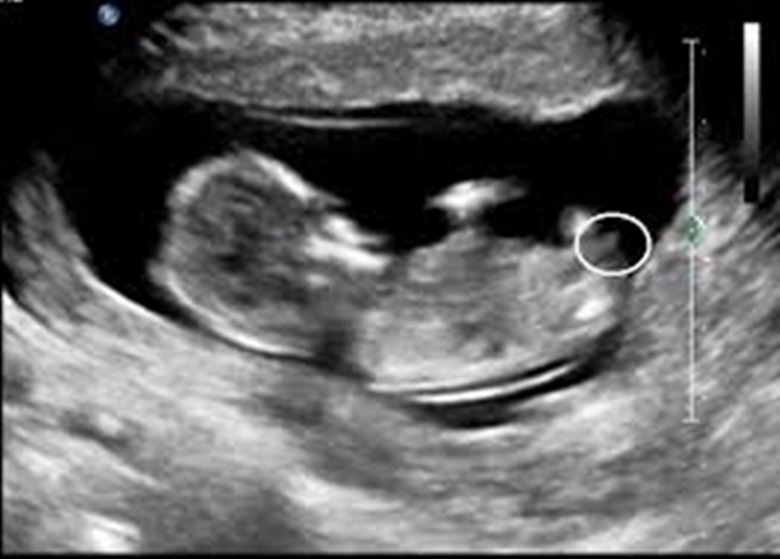

Uzman SühaN Administrator 5 Aralık 2016 #27 Görsel net değil .Değerlendirme yapabilmek için resmin aşağıda ki gibi net olması lazım..